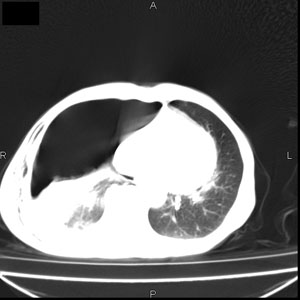

患者男,77岁,于3日前从树上摔下,头部查ct示蛛血,硬膜下出血,上腹部ct未见明显异常,右侧胸腔积液,左侧如常。肺部拍片示右侧肋骨多发骨折住院后今日来查肺部ct,我看到的是1。右侧胸腔血气胸并右肺上叶,中叶压缩性肺不张,2。右肺下叶肺挫伤并多发肋骨骨折,肌内及皮下积气3。左侧少量胸腔积液,我想请教的是3天前左侧胸腔里没有积液今天怎么出现了呢,是什么原因呢?请讨论。

回复楼主   左侧液气胸,液体来源1、肯定有血液成分,多少不一定。2、胸膜腔渗液,由于肺压缩、活动度下降,肯定胸膜吸收有问题,导致积液增多。

因为3天前病人刚摔的时候,左侧胸腔受伤不严重,故而当时没有胸腔积液,但病人受到这么大的伤害,胸膜腔内的液体动态平衡肯定会受到影响,所以过一段时间后才出现胸腔积液。

1、外伤出血需要一定的时间

2、气胸存在时间长了,产生的胸膜渗液